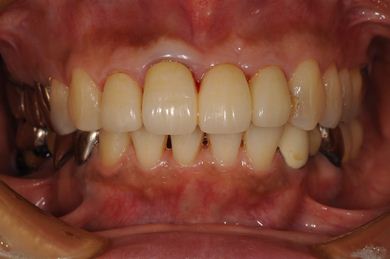

インプラントの症例写真 IMPLANT

インプラント治療+セラミック治療

| 性別/年齢 | 女性 / 52歳 | ||||||||||||||||||||||||||||||||

| 主訴 | 上の前歯の左側の1本が下がって来て歯ぐきに時々炎症がある。右側下の歯ぐきに時々炎症及び鈍痛がある。 | ||||||||||||||||||||||||||||||||

| 治療内容 | インプラント2本、オールセラミック4本(ジルコニアフレーム、オールセラミック用の土台1本) | ||||||||||||||||||||||||||||||||

| 総治療費 | 1,299,000円 | ||||||||||||||||||||||||||||||||

| 治療期間 | 7ヶ月 |